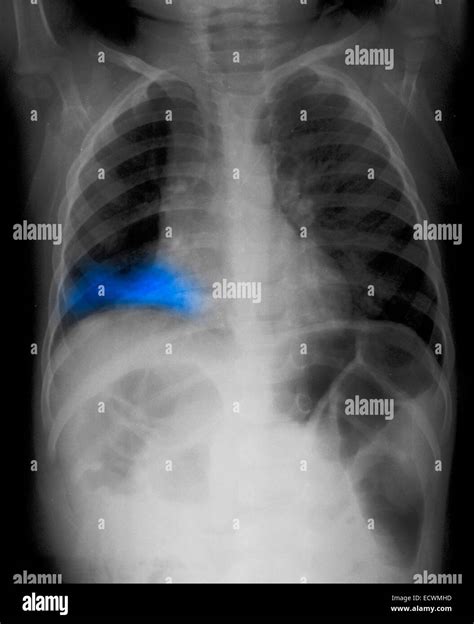

To a radiologist, a healthy lung appears mostly black on an X-ray because it is filled with air, which does not block X-ray beams. However, when pneumonia is present, the affected area of the lung becomes filled with inflammatory fluid and cells. This change in density causes the area to appear as white or grey patches, technically known as “opacities” or “infiltrates.”

• Consolidation: This refers to a solid white area where the air sacs are completely filled with fluid.

• Identifying Complications: Imaging can reveal if the pneumonia has led to a pleural effusion (fluid around the lung) or an abscess.